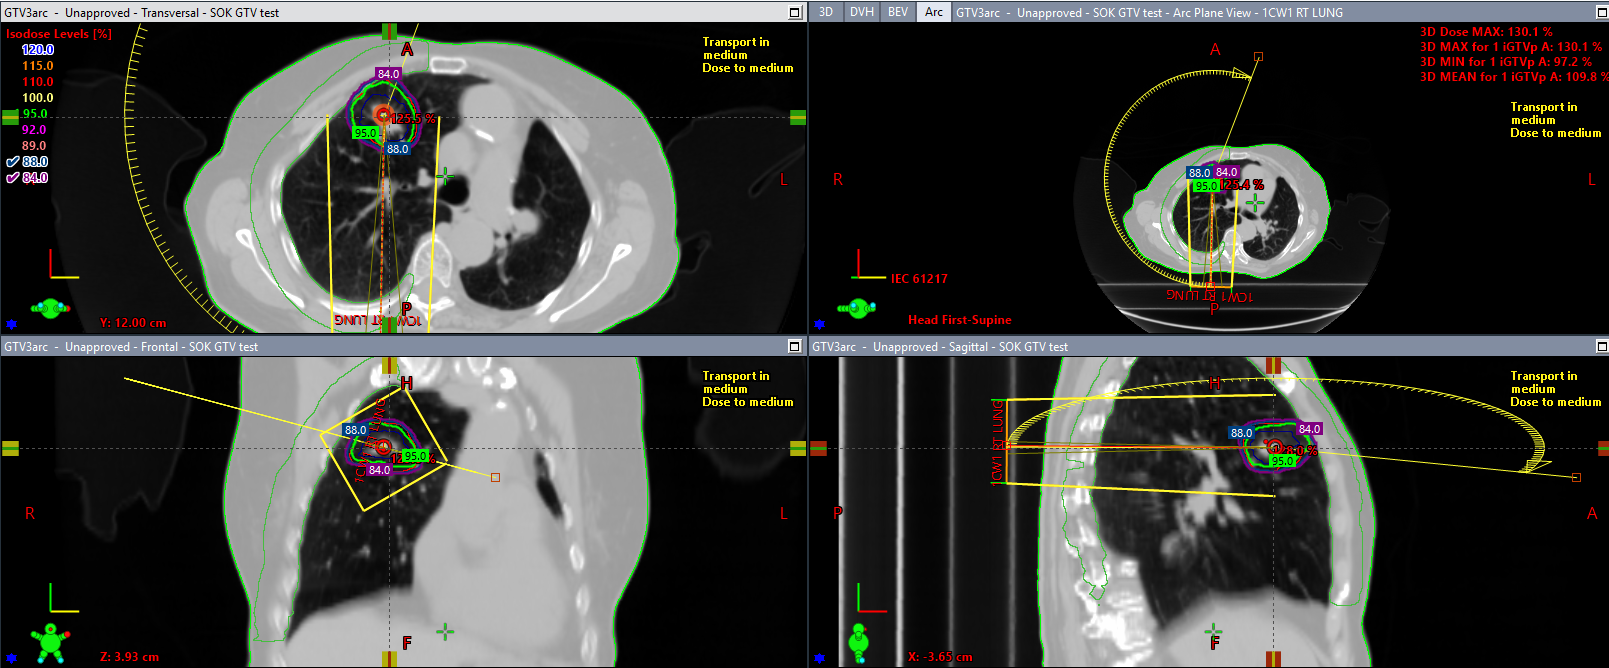

Over his career, Professor Armstrong has authored numerous peer-reviewed publications, lectured extensively, and mentored emerging clinicians and researchers. He has been instrumental in the enrolment of over 2,080 patients into clinical trials at SLRON—a significant national milestone. He currently leads the 18-33 Source Trial, a pioneering investigator-initiated study focused on advanced radiation techniques, which IRROG is supporting for national rollout.

With a team comprising clinicians, a research radiation therapist, and an administrator, Dr Mihai has led or participated in 19 national and international radiotherapy trials. Her academic focus includes stereotactic ablative radiotherapy and technical innovations in lung cancer, with publications in high-impact journals. She plays a vital role in strengthening academic-industry partnerships and expanding access to cutting-edge trials for Irish patients.